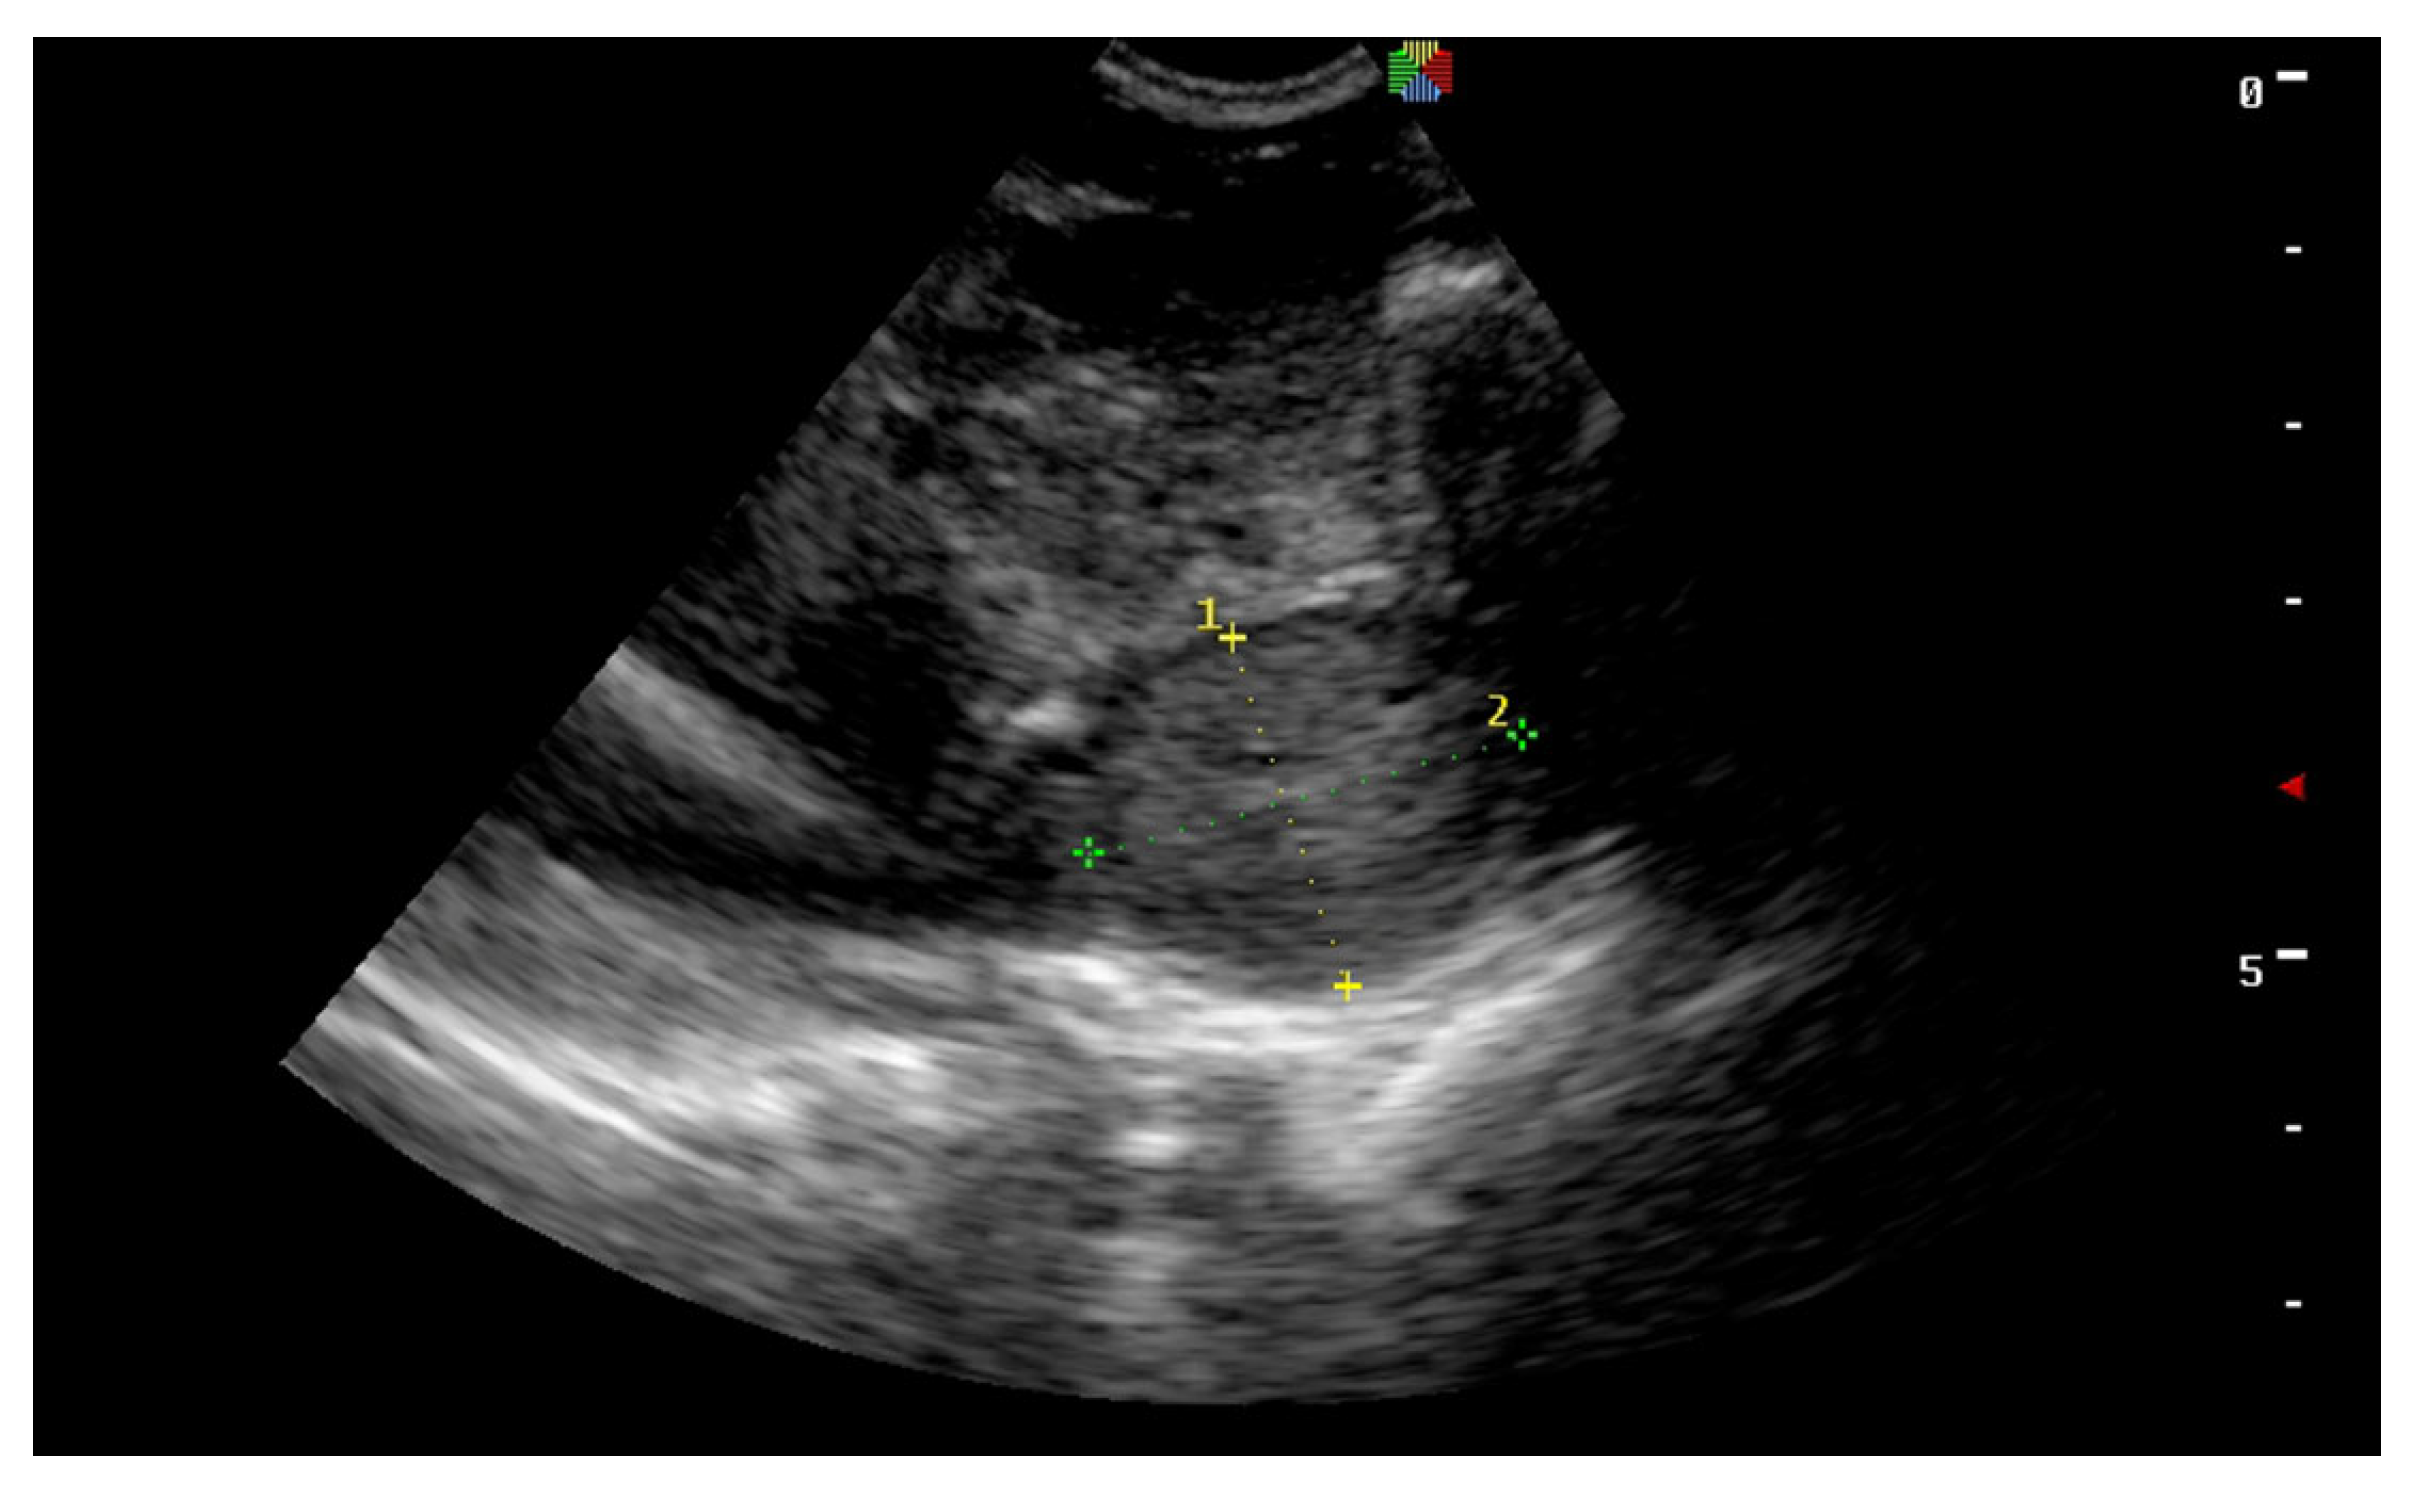

6. Asymmetric Testis/Testicular Degeneration

2.1. History and Physical Examination